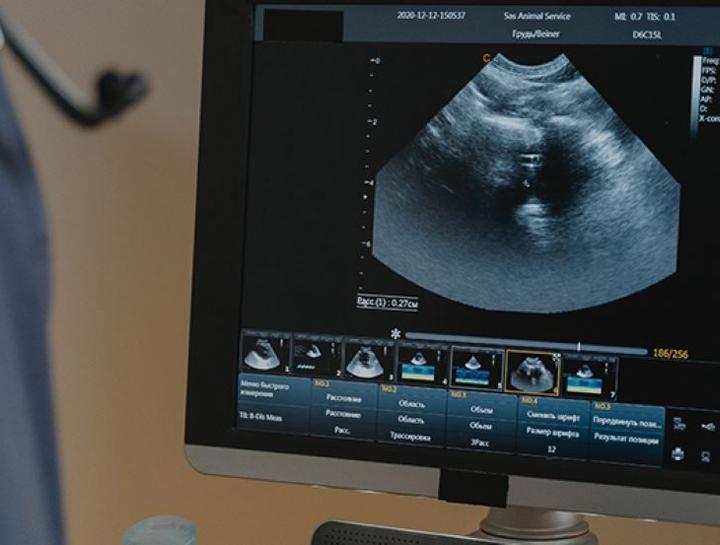

Pet Ultrasound

A non-invasive way to diagnose sick & injured pets.